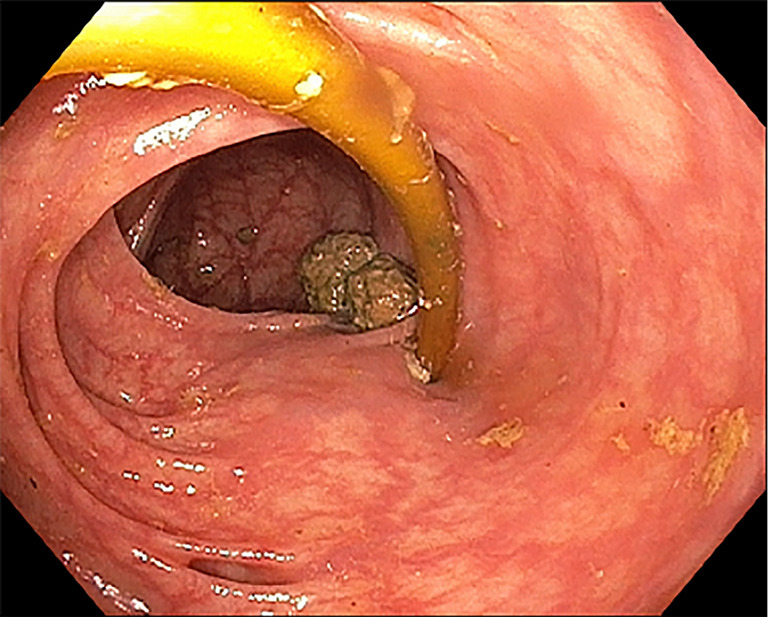

Case description: In our present case, we report on an asymptomatic patient with intraluminal penetration of the dislodged adjustment tube into the colon 26 years after implantation of a gastric banding system. We revealed the complication randomly by positron emission tomography-computed tomography (PET-CT) in the course of a tumor staging of a newly diagnosed lung cancer. The gastric band was removed laparoscopically, the adjustment tube however, had to be cut through due to extended adhesions and could only partially be removed. The rest of the catheter passed spontaneously via rectum on the following day.